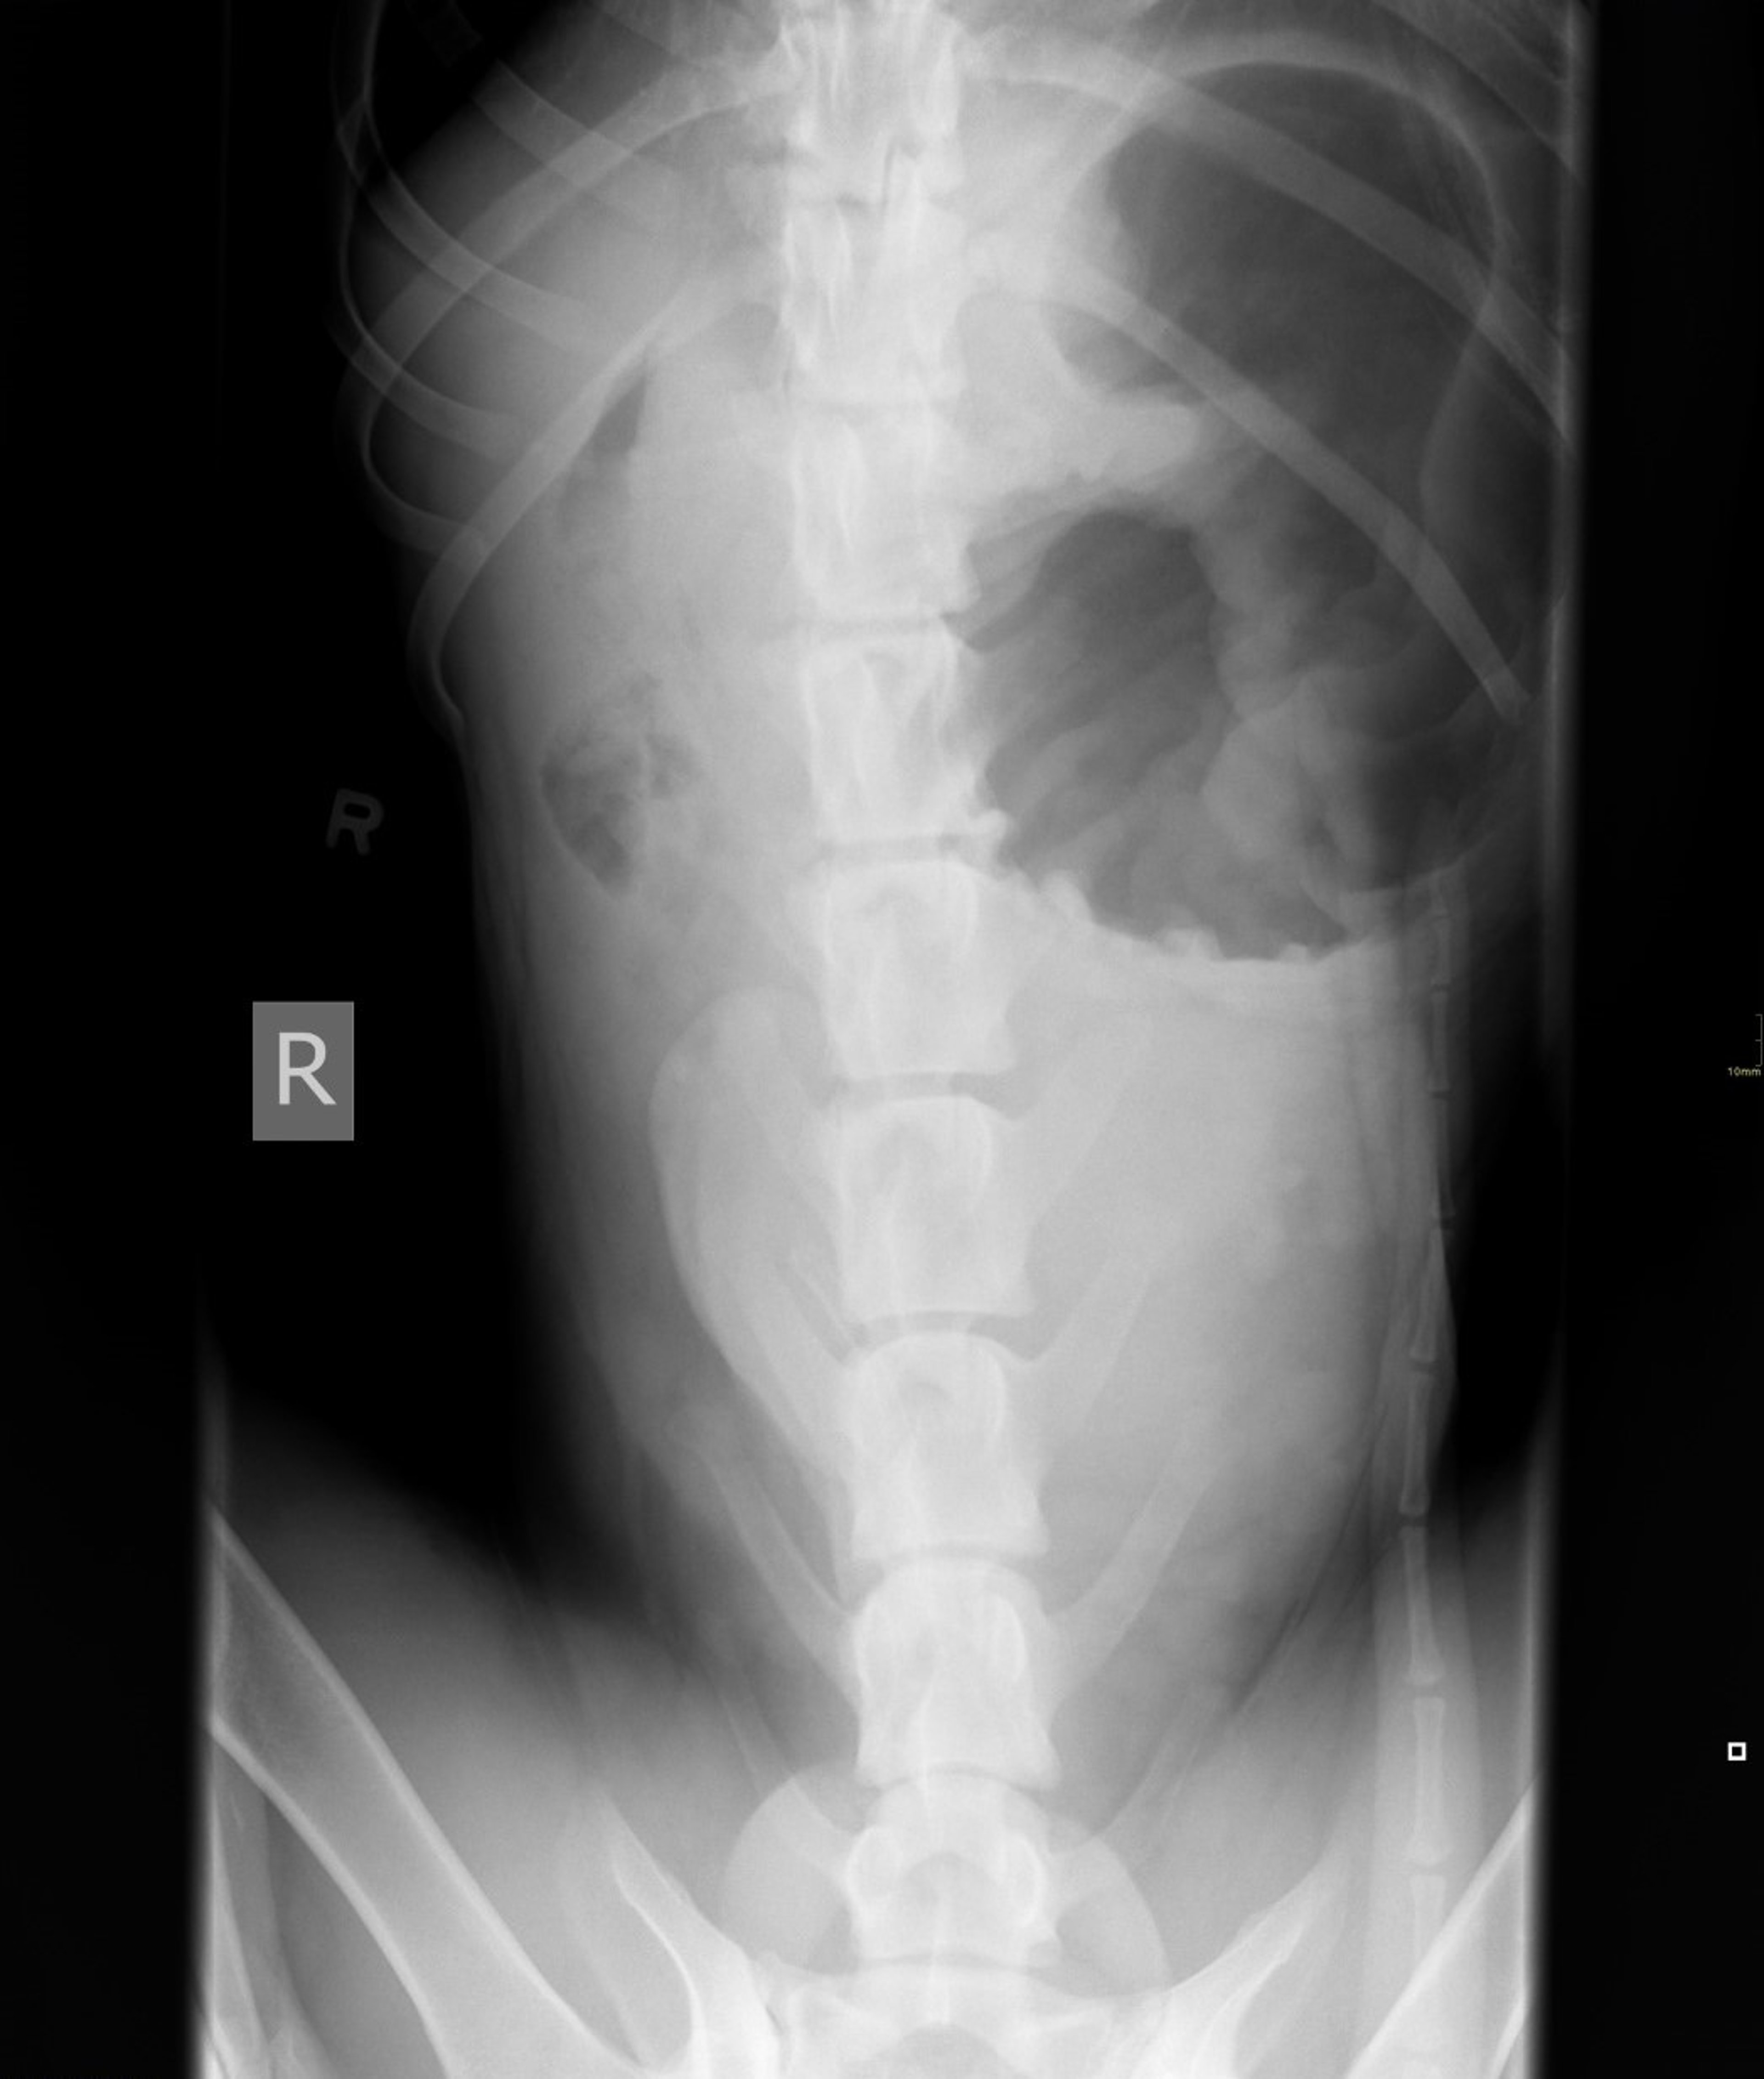

Gastric dilation and volvulus, dog, ventrodorsal view

Ventrodorsal radiograph of a 2-year-old Great Dane with gastric dilation and volvulus.

Courtesy of Dr. Thomas Gibson.